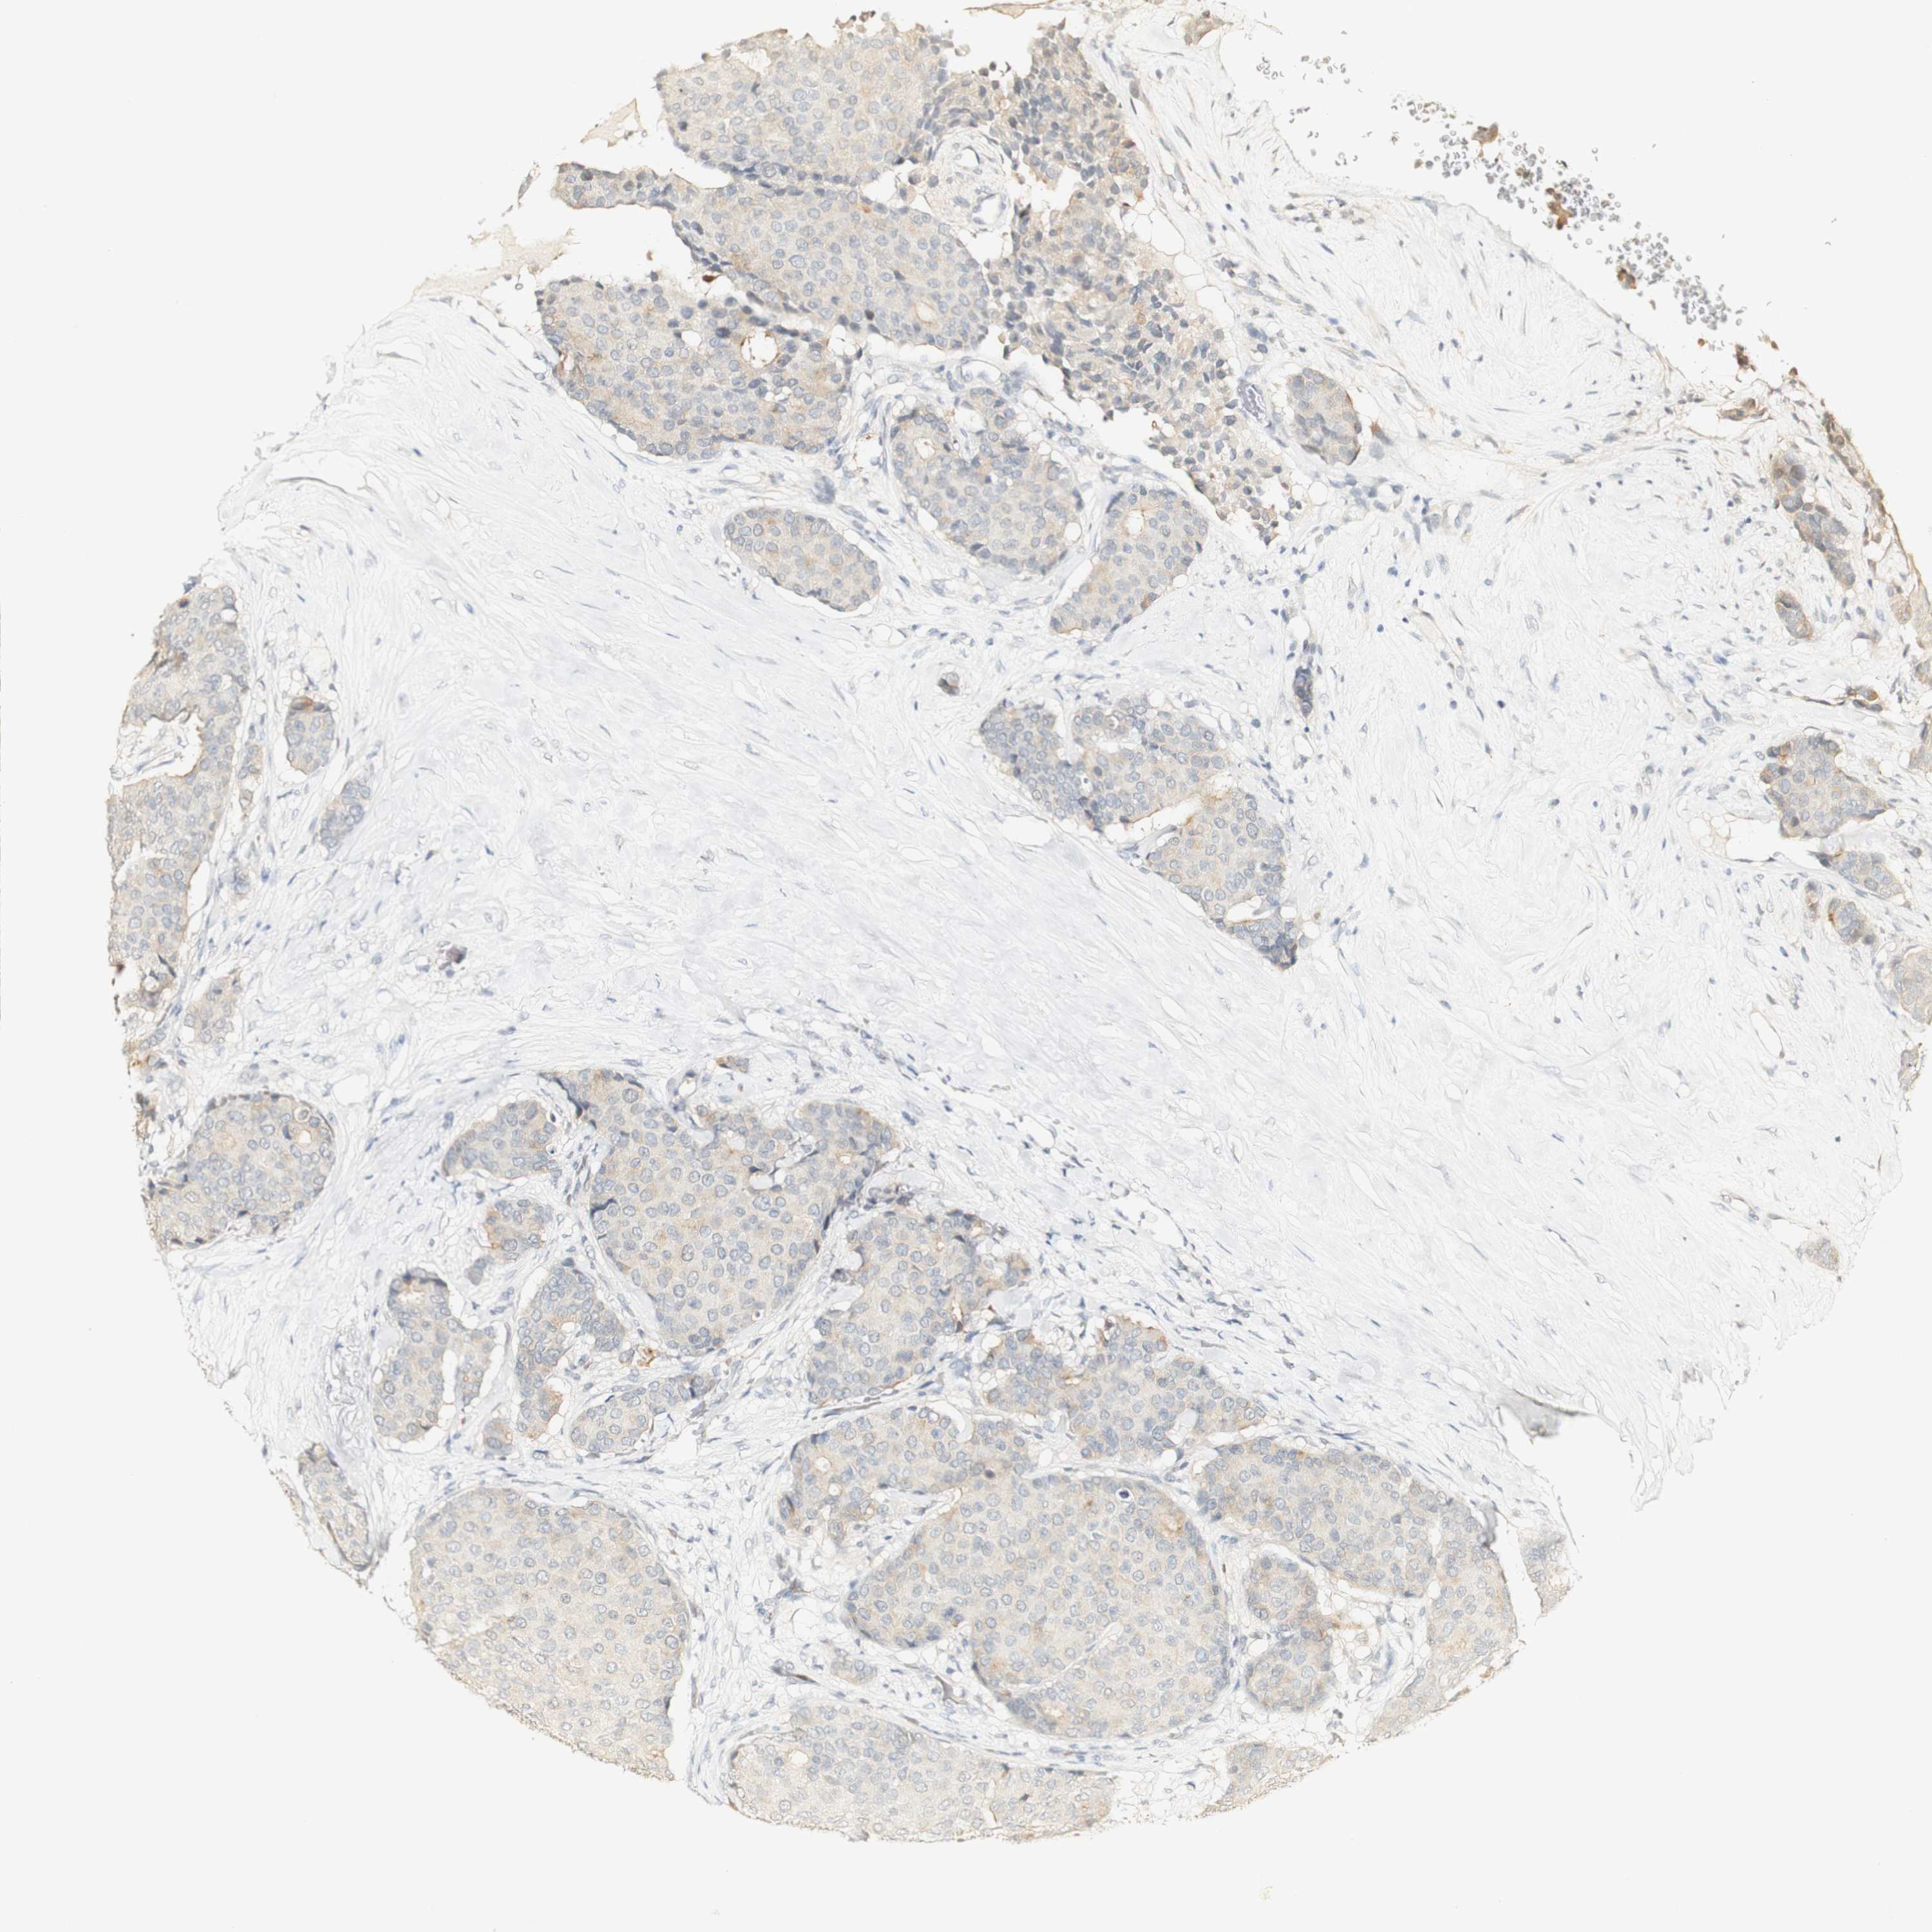

BRCA TCGA BRCA VALIDATION PROTEIN EXPRESSION

Breast cancer

Human cancer

Breast invasive carcinoma